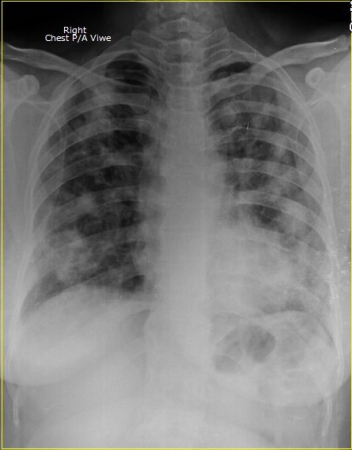

আপনাদের বোঝার সুবিধার্থে আক্রান্ত রোগীর বুক ও সাধারণ রোগীর বুকের দুইটি এক্সরের ছবি নিচে দেওয়া হলোঃ

সাধারণ রোগীর ফুসফুস বা LUNGS ।

আসুন সচেতন হই। এবং নিয়মিত স্বাস্থ্য পরিক্ষা করে দেহের ভেতরের সকল অংশের খোজ খবর রাখি। যে পরীক্ষাটি করালে আপনারা মোটামোটি ধারণা পাবেন, বা আপনার ফুসফুসে করোনা ভাইরাসের উপস্থিতি আছে কি নেই। সেটি হলোঃ CXR P/A Viwe. কারণ ভাইরাসটির প্রধান খাবার হচ্ছে ফুসফুস বা LUNGS ।আর এই পরিক্ষাটি জুড়েই রয়েছে ফুসফুসের অবস্থান।